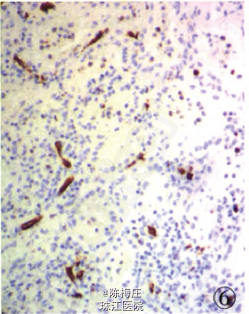

初步诊断:子宫肌瘤,子宫腺肌病,盆腔多发肿物性质待查。 确定诊断:盆腔腹膜脾组织植入。 完善相关检查,行全子宫切除术。病理检查:眼观:全切子宫1个,13 cm×8 cm×5.5 cm大小,子宫做多个切面,在肌层内查见2个大小不等灰白色肌瘤,肌瘤面积O.3 em×0.2 cm—l cm×0.66cm,肌瘤切面质韧,灰白色,呈编织状,边界清;内膜光滑,厚0.2—0.3 em,肌层厚2.5—3.5 cm,部分呈海绵状,子宫颈光滑,切面质韧,质地较细。盆腔内不规则肿物1个,灰红色,表面结节状,11cm×7.5 cm×3.5 cm大小,做多个切面,切面见多个结节,结节面积:0.4cm×0.3 cm~4.3 cm×2.5 cm,结节切面质脆,灰红色,质地细,结节边界清。另送圆形结节5个,直径1~3 cm不等,切面性质同盆腔较大肿物,均有包膜(图1)。镜检:患者子宫检查为子宫肌瘤,子宫腺肌病,病变无特殊性。盆腔多个肿物病变性质基本一致,为扩张血窦样组织,窦腔内充满红细胞,似脾红髓淤血(图2),在血窦样组织间有大小不等、发育良莠不齐的白髓样结节,结节较大者有小中央动脉(图3),结节较小者中央动脉不明显,内皮细胞无异型性,细胞分化均无异性,无病理性分裂象。可见玻璃变性纤维结缔组织似脾小梁样结构(图4)。免疫表型:血窦样内皮细胞nFli-1强阳性(图5),CD31弱阳性;CD34肿物小血管强阳性而血窦内皮细胞阴性(图6),CR和SMA均阴性;Ki-67增殖指数为5%。